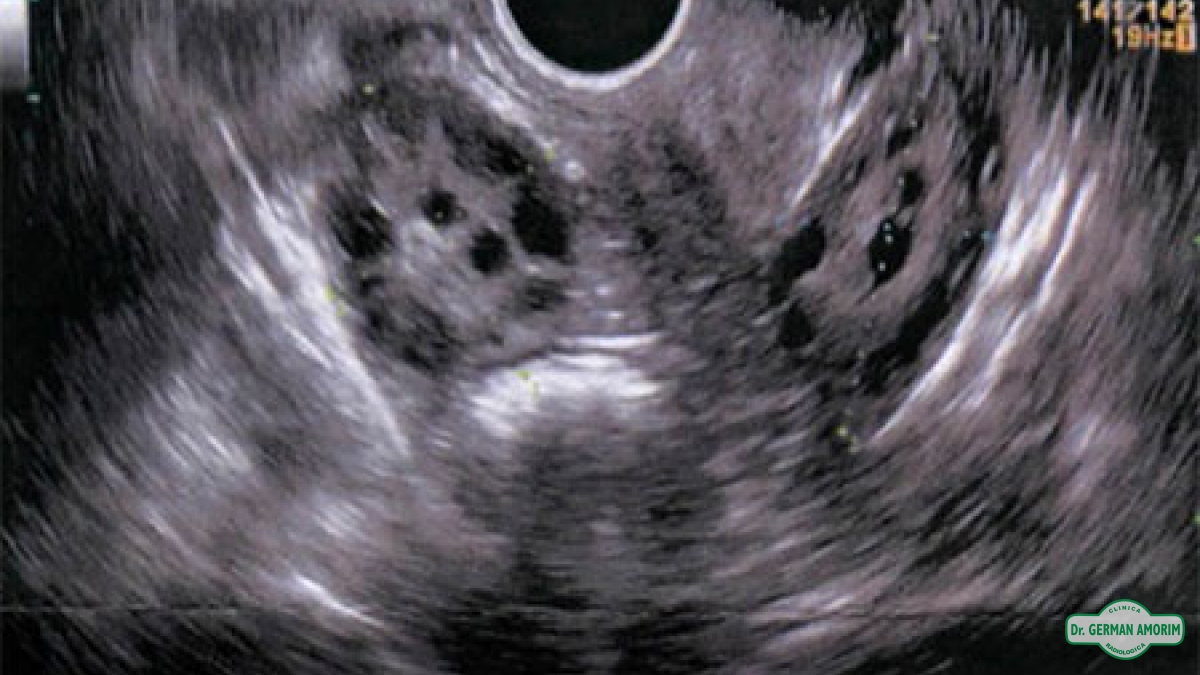

El folículo antral (en reposo) es una pequeña esfera llena de líquido que contiene un óvulo inmaduro. Los folículos son visibles y pueden contarse mediante una ecografía los días segundo, tercero y quinto del ciclo menstrual. El número de folículos antrales varía cada mes.

El recuento de folículos antrales, junto con la edad y el perfil hormonal del día 3, es uno de los mejores indicadores de la reserva ovárica y de la capacidad de que la mujer consiga la gestación con la fecundación in vitro (FIV). Dicho de otro modo, los folículos antrales predicen el número de folículos maduros (dominantes) que podremos estimular con los medicamentos que se administran antes de la FIV. El número de óvulos que obtengamos guarda relación directa con las tasas de éxito de la FIV.